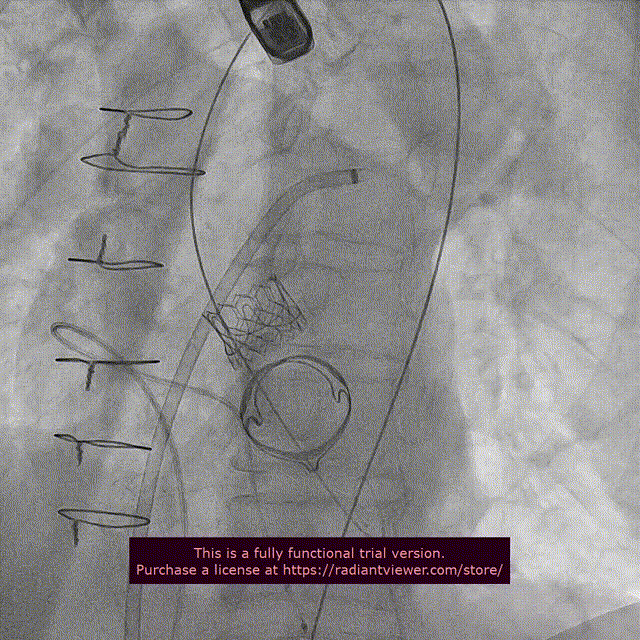

SAPIEN 3瓣膜跨二尖瓣生物瓣

二尖瓣生物瓣位SAPIEN 3瓣膜释放